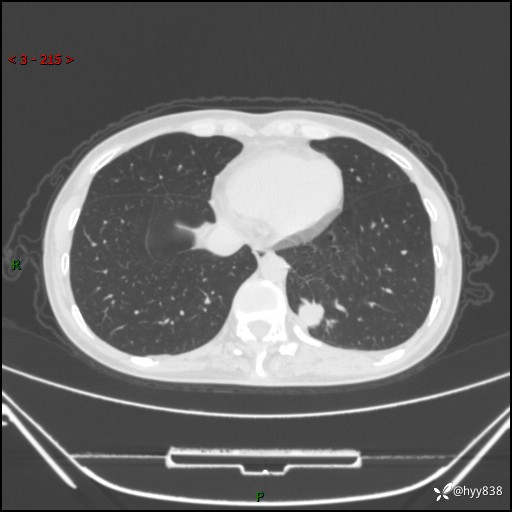

增强动脉期+静脉期

各期CT值:48hu 65hu 76hu